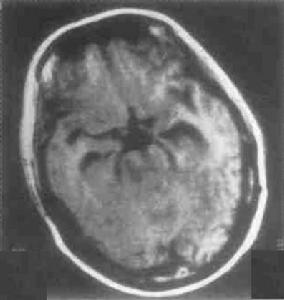

(1)早期(炎症反應期):膠原纖維少呈等密度,不顯示腫塊,周圍為低密度腦水腫,在額葉呈“漏斗狀”,在顳枕頂區呈“三手指狀”,強化不均勻。

(2)中期(炎症消退期):膠原組織增殖內含乾酪樣物質,呈小盤狀高密度周圍是低密度腦水腫,呈明顯環狀強化。